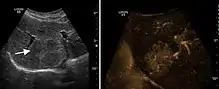

HCC appearance on 2D ultrasound is that of a solid tumor, with imprecise delineation, with heterogeneous structure, uni- or multilocular (encephaloid form). An "infiltrative" type is also described which is difficult to discriminate from liver nodular reconstruction in cirrhosis. Typically HCC invades liver vessels, primarily the portal veins but also the hepatic veins . Doppler examination detects a high speed arterial flow and low impedance index (correlated with described changes in tumor angiogenesis). The spatial distribution of the vessels is irregular, disordered. CEUS examination shows hyperenhancement of the lesion during the arterial phase. During the portal venous phase there is a specific "wash out" of ultrasound contrast agent (UCA) and the tumor appears hypoechoic during the late phase. Poorly differentiated tumors may have a stronger wash out leading to an isoechoic appearance to the liver parenchyma during portal venous phase. This appearance was found in approx. 30% of cases. The described changes have diagnostic value in liver nodules larger than 2 cm.